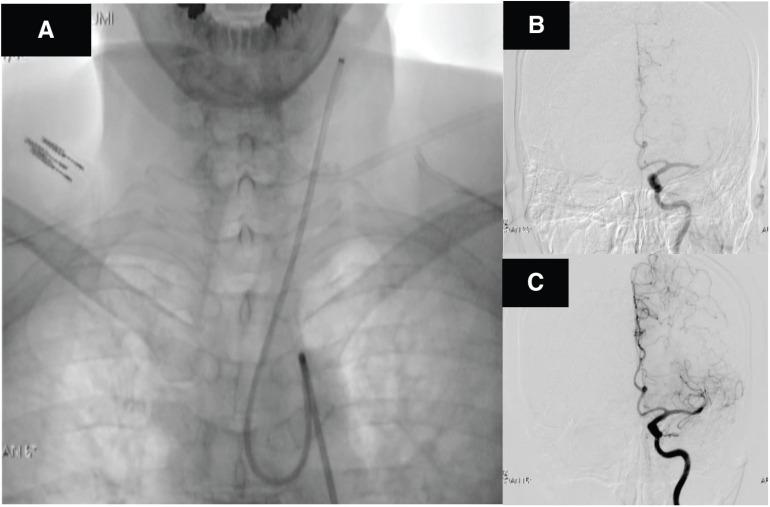

The purpose of this study was to evaluate the combination of a 100-cm long balloon-guiding catheter (BGC) and 40-cm long sheath in patients treated by mechanical thrombectomy for anterior circulation acute ischemic stroke.

The subjects were 77 consecutive patients treated by endovascular recanalization for anterior circulation occlusion from January 2011. After February 2018, 24 patients were treated by mechanical thrombectomy using a long BGC and long sheath (L-BGC group), and were compared with 53 patients treated before January 2018 using a normal BGC and sheath (S-BGC group). The baseline angiographical/clinical characteristics, main procedures, BGC insertion time, internal carotid artery (ICA) cartelization rate, recanalization rate, and clinical outcome were compared between L-BGC and S-BGC groups.

There was no significant difference in angiographical/clinical characteristics except for intravenous thrombolysis with recombinant tissue plasminogen activator (IVrtPA) treatment. In all, 22 patients were treated by combined technique (CoT) thrombectomy in the L-BGC group. The BGC insertion time was significantly shorter in the L-BGC group than in the S-BGC group (19 vs 13 minutes), and ICA catheterization of BGC was successful in the L-BGC group, whereas there were seven failures in the S-BGC group (100% vs 84%). The puncture-to-recanalization (PtoR) time was significantly shorter in the L-BGC group (90 vs 44 minutes). The successful recanalization (SR) rate was higher in the L-BGC group (96% vs 72%). Good outcomes (mRS 0-2) slightly increased in the L-BGC group (64% vs 49%). In the multivariable analysis, only CoT thrombectomy was associated with PtoR and SR.

The combination of a long BGC and long sheath results in rapid and stable BGC insertion to the ICA. CoT thrombectomy with these devices may be useful for SR and reducing the PtoR in anterior circulation mechanical thrombectomy.